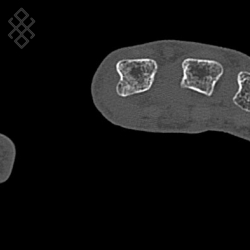

Scanner de la Main